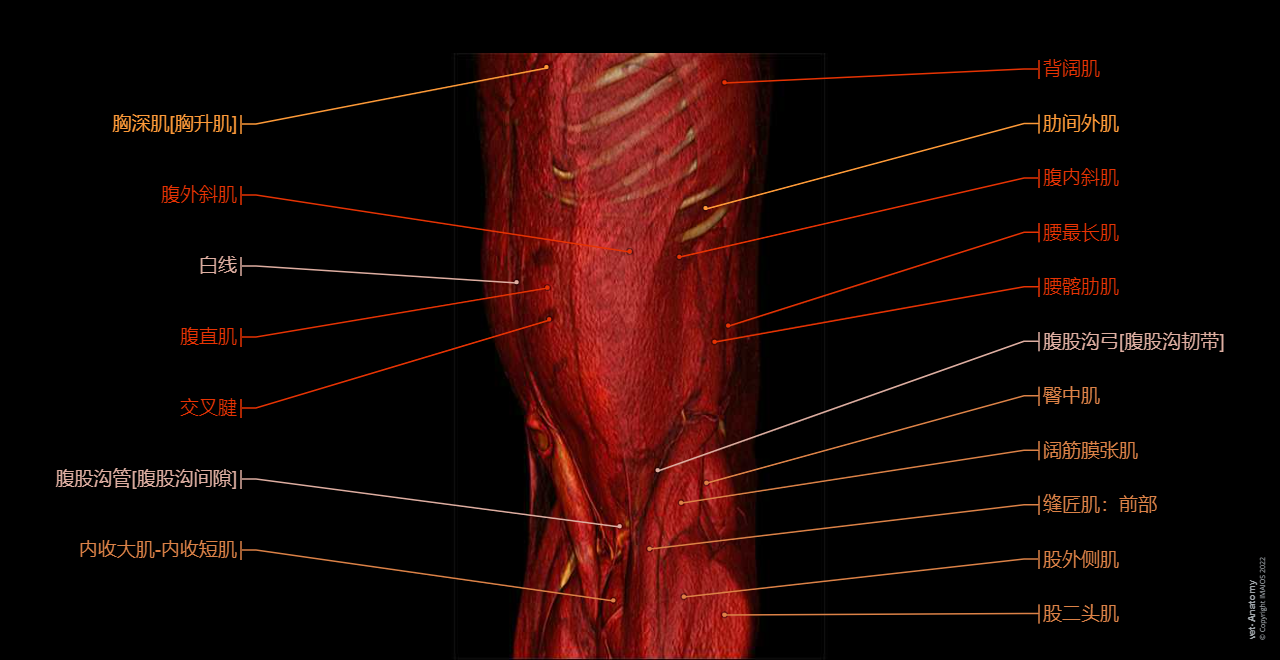

vet-Anatomy兽医图集的本模块是关于CT扫描的犬类腹部和骨盆。

CT图像来自一只健康的6岁阉割雄性犬。

在vet-Anatomy动物图集的此模块中,计算机断层扫描(CT)显示了标有解剖结构的犬科腹腔和骨盆横截面,并用3D图像显示犬科腹部。

CT图像存在3个平面方向(横向,矢状和背侧),并且使用两种对照方式(软组织/血管和骨骼)展现。本模块的末尾提供其他3D解剖图像,便于进一步了解犬科总体解剖结构,展示了骨骼、内脏(肝脏、脾脏、胰腺、消化道)、泌尿生殖系统、动脉、全身静脉系统(主要是尾腔静脉及其分支)、门静脉系统、肌肉和表面解剖的三维容积透视图。

三维容积透视图是由Antoine Micheau博士在GE ADW上使用相同的CT医学影像成像数据而创建。

Abdomen and pelvis anatomy of the dog on CT - Anatomy atlas - 3D: Myology - Muscles of abdomen - Muscles of the tail [coccygeal]

Abdomen and pelvis anatomy of the dog on CT